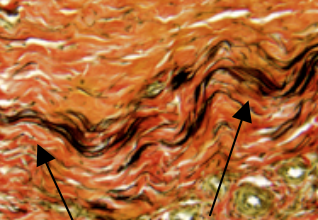

What are the properties of this fibre?

Elastic Stretchable, elastic Yellow fibrous tissue eosinophilic in H&E black in verhoeffs stain